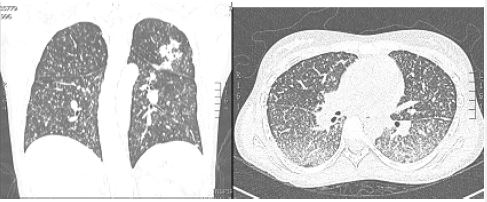

El reporte de las biopsias mostró inflamación crónica activa severa, ulcerada, con granulomas sin necrosis caseosa, por lo cual se le indicaron coloraciones especiales Ziehl-Neelsen, Ziehl-Neelsen modificado (estas para descartar presencia de bacilos ácido alcohol resistentes y coccidias), tinción de PAS, tinción de plata metenamina de Grocott (estas para descartar presencia de hongos patógenos); además, inmunohistoquímica de citomegalovirus. Todas estas pruebas resultaron negativas. Se le dio el alta hospitalaria con sospecha de EC. Se dejó tratamiento con prednisolona a 40 mg por día durante 2 semanas, luego una reducción gradual de 5 mg cada semana hasta suspender. En estudios adicionales, se le realizó una cápsula endoscópica, que indicó una ulceración estenosante en yeyuno. Los reactantes de fase aguda como la velocidad de sedimentación globular, 41; reacción en cadena de la polimerasa, 2,5 (VR hasta 0,8), y calprotectina fecal, 1100 µg/kg/heces (VR 50 µg/kg/heces), se encontraban elevados. Con estos hallazgos se decidió reducir el intervalo de aplicación del adalimumab a 40 mg cada semana, y se le añadió azatioprina a dosis de 2 mg/kg/día (150 mg/día). Un mes después del inicio de este tratamiento, presentó un cuadro de fiebre, diaforesis nocturna, tos seca, por lo cual se hospitalizó y se diagnosticó con tuberculosis miliar ( figura 2). Múltiples adenopatías mesentéricas (con evidencia de granulomas caseificantes), y con evidencia de actividad endoscópica. El diagnóstico microbiológico fue mediante fibrobroncoscopia y lavado bronquioalveolar (secreciones pulmonares).

En ese momento, estaba con el tratamiento inmunosupresor con adalimumab y azatioprina; por ello, se decidió suspender. Además, se inició tratamiento con terapia antituberculosa con isoniacida (300 mg), rifampicina (600 mg), pirazinamida (1500 mg) y etambutol (1200 mg): durante los 2 primeros meses, luego continuó a 2 veces por semana por 6 meses más. Desde las 2 primeras semanas mejoraron sus síntomas generales (fiebre, malestar y escalofríos), al igual que sus síntomas digestivos. Un poco antes del mes mejoraron los síntomas respiratorios. A las 8 semanas estaba asintomático, aumentó de peso y tuvo una mejoría marcada de su estado anímico. Se le realizó control endoscópico a los 6 meses de tratamiento, con curación endoscópica.